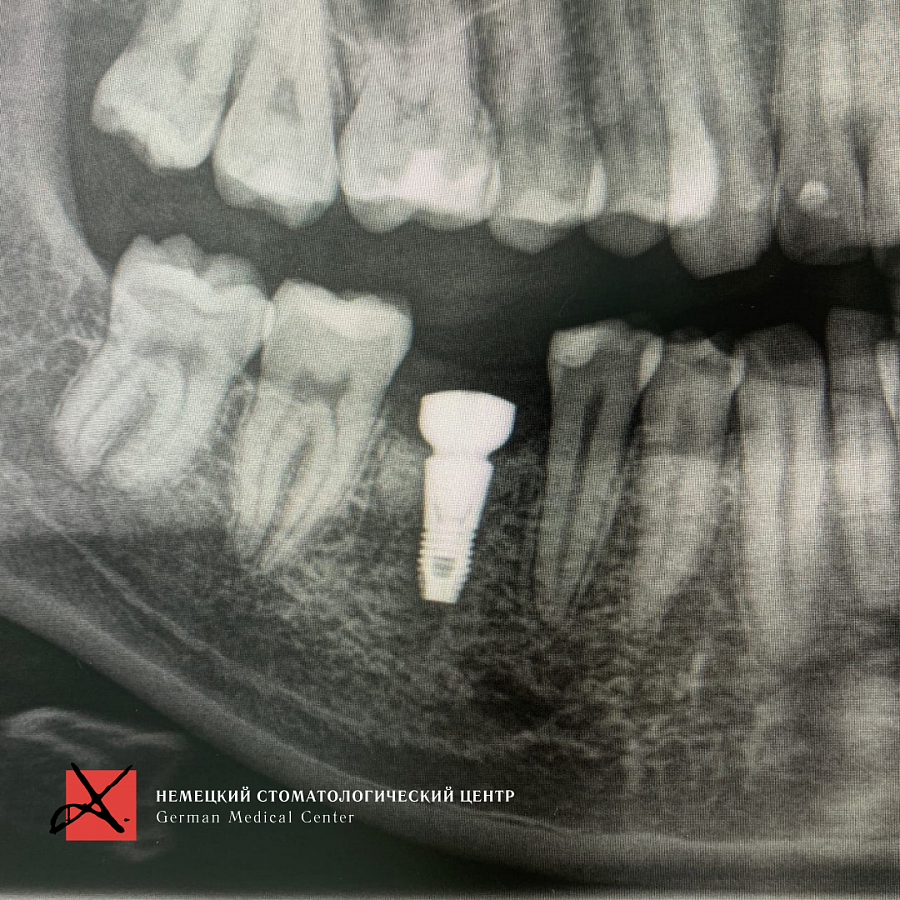

Пациент направлен врачом-терапевтом для удаления зуба 46 (нижний шестой зуб справа) и одновременной постановки имплантата.

Зуб был фрагментирован, чтобы удаление прошло максимально атравматично, то есть без повреждения окружающих костных стенок. После удаления установлен имплантат. Операция прошла успешно, пациенту уже установлена зубная коронка.